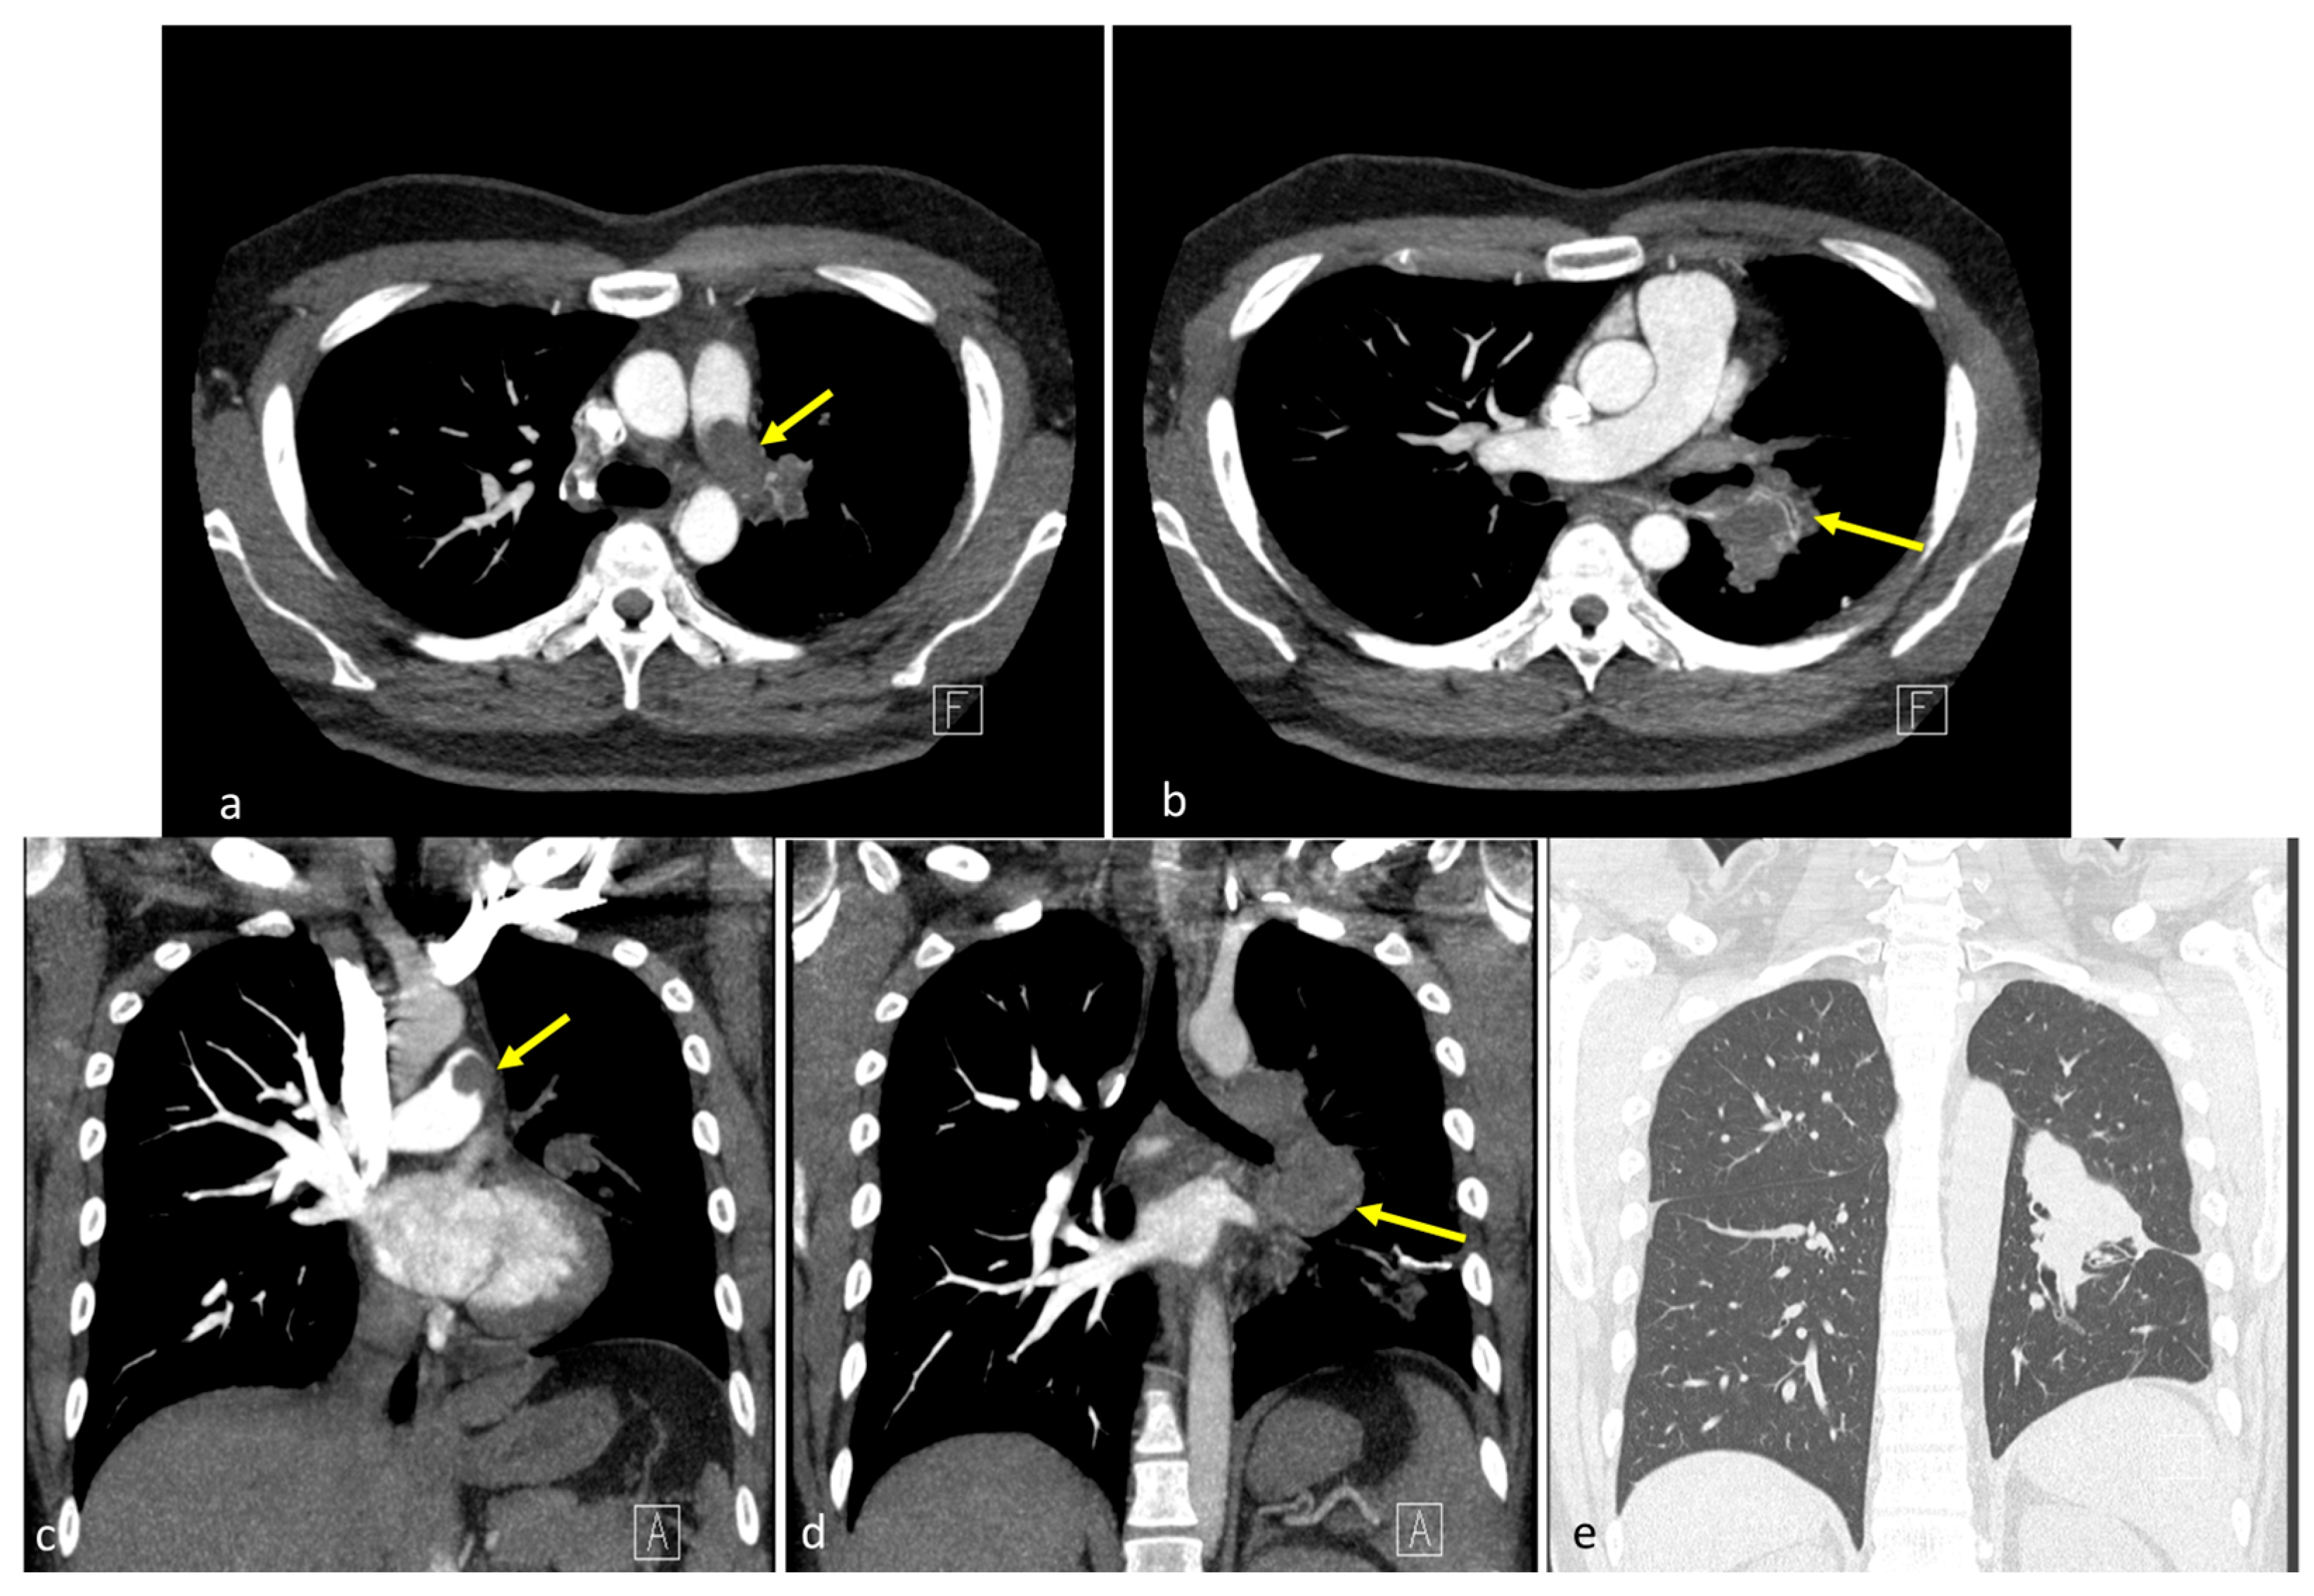

Figure 1. Preoperative computed tomography findings. (a,b) Coronal images revealed a 7.1 cm lobulated, heterogeneous mass spanning the upper left and lower lobes, extending medially into the pulmonary hilum (yellow arrows) [1,2,3]. The left pulmonary artery was encased with intraluminal lobulated filling defects, forming acute angles with the vessel wall, with suggested tumor thrombus. No pleural effusion or mediastinal shift was observed. (c,d) Axial sections showed a centrally located soft tissue mass with irregular margins involving the left hemithorax, with mild post-contrast enhancement and direct invasion into the left pulmonary artery. Intraluminal filling defects contiguous with the mass were identified. (e) Regarding lung window settings, the mass appeared as a dense, ill-defined opacity occupying the central left hemithorax, merging into the adjacent lung parenchyma. The letters “A” and “F” on the images represent standard orientation markers indicating anterior (A) and foot (F) directions, respectively.